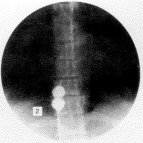

3.3 治疗效果的判定 球囊扩张手术效果一般根据手术前后静脉压的变化以及造影结果判定,但单凭静脉压降低难以判断狭窄是否完全扩开,故笔者采取在扩张中观察到的直观影像来判断扩张效果和作为终止手术的指征:当扩张开始时,由于膜对球囊的束缚,球囊形成“8”字形(见封三图2),继续加压,“8”字凹陷消失,反复几次后,如果从电视监视屏上观察到从加压开始,球囊即由小到大呈均匀性扩张,没有出现中间缩窄环或局限性压痕,就可以考虑狭窄已基本扩开(见封图3a),可将造影剂抽出少许,使球囊略缩小,上下移动导管,观察有无阻力,如无明显阻力,则进一步证实狭窄已完全扩开,则可中止扩张,抽空球囊,在原狭窄下方造影,可见造影剂被快速的血流冲击迅速散开呈云雾状进入右房(见封三图3b),术前锥形狭窄影像消失,如更换导管行快速加压造影效果更为满意。

图2 扩张时,膜状狭窄束缚球囊形成8”字形